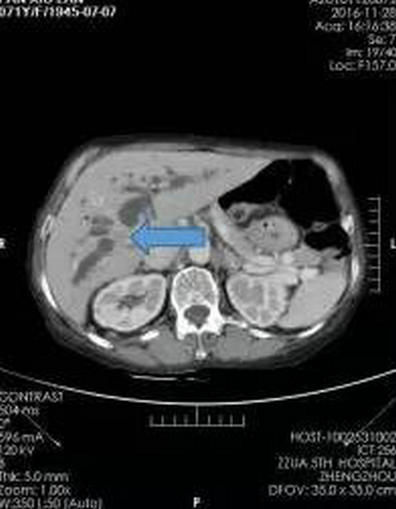

入院SCT增强扫描(箭头所指为肿瘤部位)